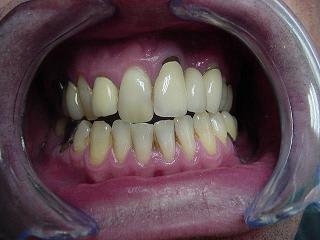

voici un cas paro qui me pose problème: Homme 39 ans, non fumeur, exellente santé ( spotif +++). PAJ dans un mauvais contexte occlusal ( bout à bout et contact essentiellement en posterieur. Je suis un peu paumé sur ce coup là! surtout sur le devenir des molaires. Des pistes avant d'en parler à nice? merci

Les mobilités sont peu importantes malgré l'image.

Pour ce qui est de regler l'occlusion, dans un tel cas, comment faire? des meulages sont impossible: trop à supprimer...